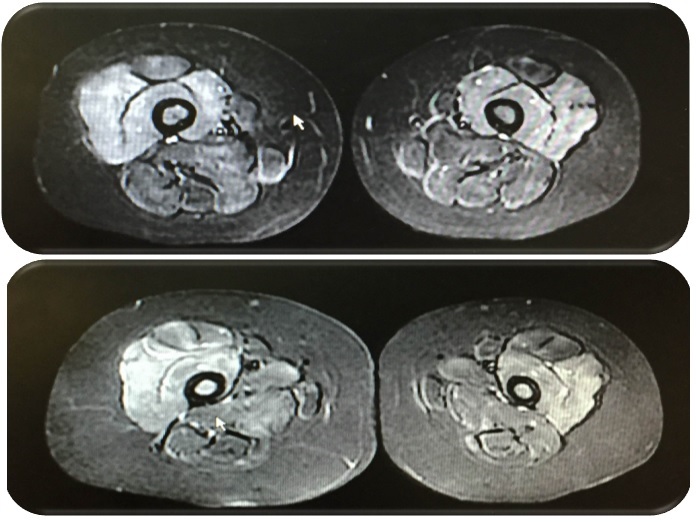

Alteración de señal de múltiples grupos musculares fundamentalmente en muslos y piernas, compatibles con la sospecha clínica de probable dermatomiositis.

• Resonancia magnética nuclear (RMN): alteración de la señal de múltiples grupos musculares, fundamentalmente en muslos y piernas, compatibles con la sospecha clínica de probable dermatomiositis.